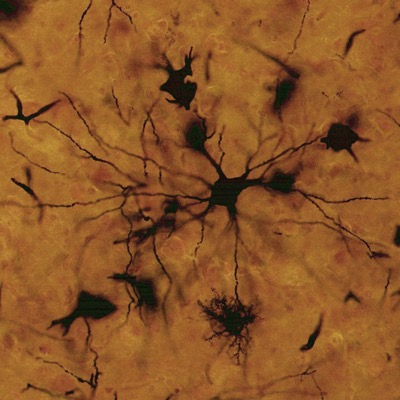

La neurona o célula nerviosa es la unidad funcional del sistema nervioso. Está compuesta por el soma que contiene el núcleo y varias evaginaciones de longitud variable. Las células gliales son células no conductoras. El SNC contiene cuatro tipos de células gliales: los oligodendrocitos, los astrocitos, la microglía y los ependimocitos. Estas células se denominan glía central. En el sistema nervioso periférico (SNP), las células de sostén se denominan glía periférica e incluyen las células de Schwann, las células satélites y otras células asociadas con estructuras específicas.

Neuronas